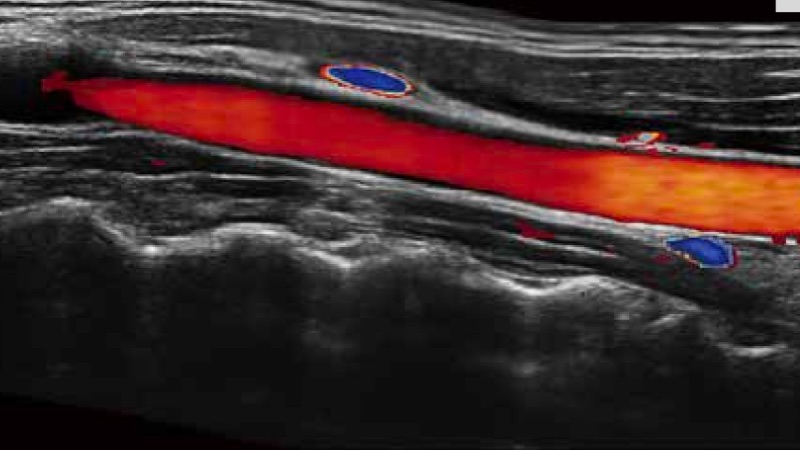

開立醫(yī)療通過不斷的技術(shù)創(chuàng)新,為大眾的生命健康提供持續(xù)關(guān)愛。P12 Plus采用全新一代超聲成像平臺,新平臺旨在將真實還原組織解剖結(jié)構(gòu)作為首要目標(biāo)。平臺采用全新集成化硬件模塊,搭載新一代芯片,系統(tǒng)性能得到大幅提升,為您的診斷提供了豐富的臨床信息。優(yōu)異的圖像表現(xiàn),豐富的探頭配置,全面的應(yīng)用功能,為您日常診斷提供了可靠的助手。